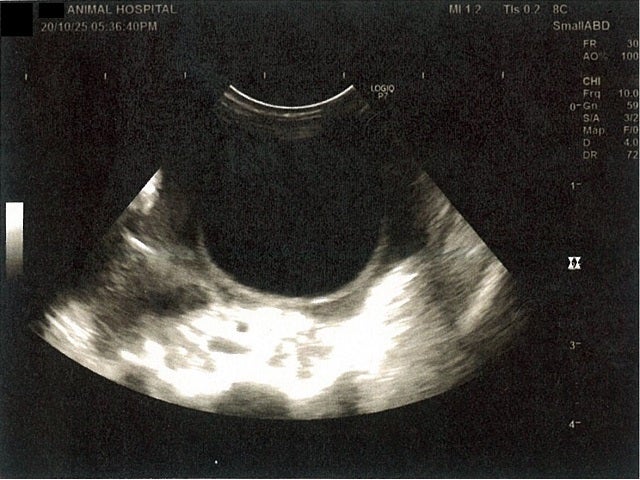

肝臓周りに腹水が確認できるエコー写真

心臓のみ腹水が確認できないエコー写真

《心臓周りの胸部以外の全ての腹部で腹水がみられるとの診断です》

大網という部分で内臓を包む膜のようなものです。その周りに腹水が溜まっています。